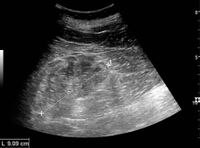

Figure 5. Simple renal cyst with posterior enhancement in an adult kidney. Measurement of kidney length on the US image is illustrated by '+' and a dashed line.[1]

Masses are seen as a distortion of the normal renal architecture. Most renal masses are simple cortical renal cysts with a round appearance and a smooth thin capsule encompassing anechoic fluid. The incidence increases with age, as at least 50% of people above the age of 50 have a simple cyst in one of the kidneys. Cysts cause posterior enhancement as a consequence of reduced attenuation of the ultrasound within the cyst fluid (Figure 5). The simple cyst is a benign lesion, which does not require further evaluation.[1]